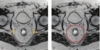

# Abdome: cólon e reto Classificação de Parks das fístulas perianais de acordo com a RM? (4)

1. Interesfincteriana – trajeto entre os esfíncteres interno e externo, o mais comum; 2. Transesfincteriana – atravessa o esfíncter externo em direção à fossa isquiorretal; 3. Supraesfincteriana – sobe acima do esfíncter externo e desce para a fossa isquiorretal; 4. Extraesfincteriana – não passa pelos esfíncteres; vai do reto diretamente à pele perianal; Temos ainda a superficial – trajeto raso, sem envolvimento dos esfíncteres (dd fissuras).

# Abdome: cólon e reto "Relógio anal" na avaliação e descrição de fístulas anorretais?

Convenção usada para descrever a localização de fístulas anorretais. ## Footnote Ex: A fístula tem abertura interna às 6h e se estende com trajeto secundário até as 9h,